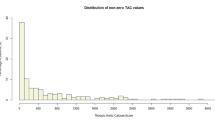

The distribution of calcium along the aorta is usually very heterogeneous. It is possible to identify coarse calcium in one segment, while there is no calcium in another segment from the same individual, as shown in Fig. 1. In the first case (images 1a and 1b), there was calcium in large amount in the arch and descending thoracic segments, while there was no calcium in the ascending aorta. In the second case (images 1c and 1d), the calcium concentration was much higher in the aortic arch compared with ascending and descending thoracic portions.

Heterogeneous distribution of calcium along the aorta. a, b CT reconstructions in the parasagittal plane. In this case, ascending aorta had no calcium (arrow in a), whereas in the arch and descending portions (arrow in b) there were circumferential plaques covering almost all aortic wall. c, d CT reconstructions in the axial plane. The most calcium concentration was in the aortic arch (arrow in c), while in ascending (superior arrow in d) and descending (inferior arrow in d) segments calcium were coarse, but sparse